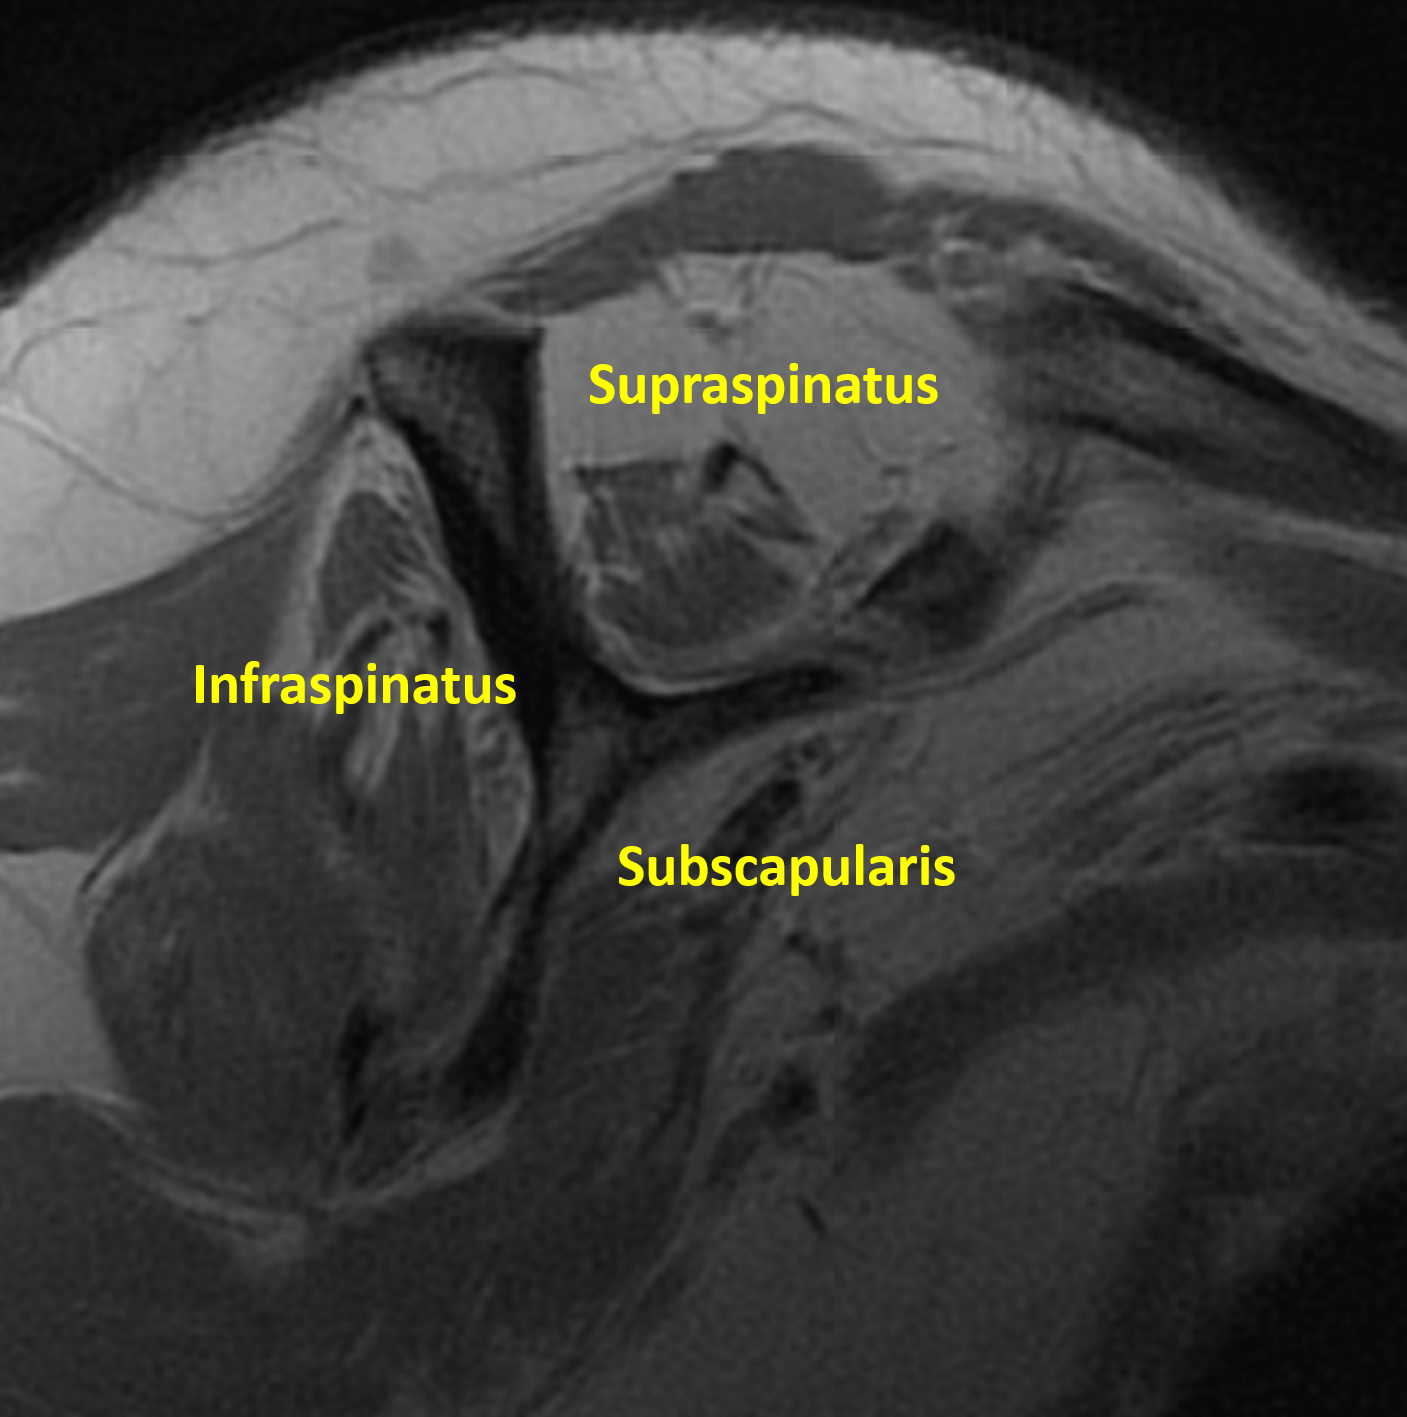

The Sagittal Plane depicts the shoulder as if viewing from the patient’s side. This plane allows a unique opportunity to see the rotator cuff muscles simultaneously and evaluate their quality. For instance, the image below depicts healthy rotator cuff muscles with appropriate size and homogenously dark color.